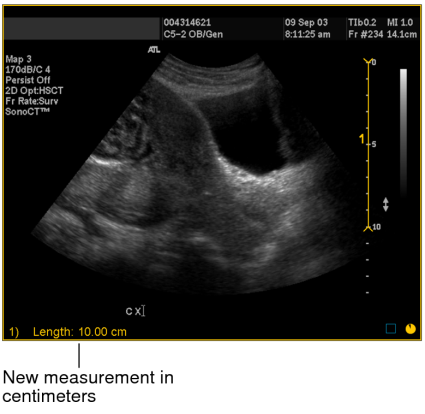

For example, in step 3 you can see that the drawn line corresponds to a length of 10 centimeters on the scale.

The image is calibrated and the length of the measurement now appears in centimeters. All subsequent linear, orthogonal, elliptical, and freehand region of interest measurements that you create on the image are calibrated according to this ratio.